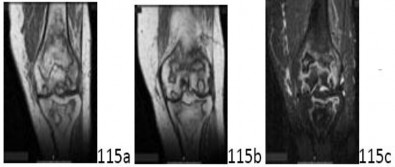

ORTHOPEDIC MCQS ONLINE OB 20 2A RECONSTRUCTION OrthoCash 2020 A 65-year-old woman with painful knee arthritis…